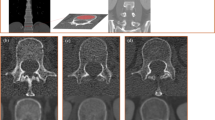

Analysis was performed on chest CT scans acquired on Acquillion One Genesis Edition (Canon Medical Systems, Otawara, Tochiqi, Japan). Contrast enhanced and non contrast enhanced CT images were acquired using a tube peak potential (KVp) of 100 and 120 KVp, respectively. The table feed was 32.5 mm per rotation (320 slice scanner with 80 × 0.5 mm collimation) with a spiral pitch factor of 0.813 and revolution time of 0.275 s using a 512 × 512 matrix. Reconstruction was performed using Adaptive Iterative Dose Reduction (AIDR3D) using an FC30 convolution kernel. CT scans were analyzed using the IDS7 viewer (version 25.3, Sectra, AB, Linköping, Sweden). Images were presented using a bone window (W:1800 L:400). Density of the vertebral body at the level of Th12 was assessed following the method as described by Pickhardt et al.12. In brief, a circular region of interest (ROI) was placed in the trabecular bone of the vertebral body stretching from the anterior part of the vertebral body (excluding cortical bone) and the basivertebral vein. One ROI for each scan was placed, in the axial image. Mean CT density (HU) was measured (Fig. 1). When placing the ROI, areas that would distort the CT density measurement (such as focal lesions, the internal posterior venous plexus or imaging-related artifacts) were avoided. Images with a slice thickness of 1.0 mm were used for analysis. Details on the assessment of bone density of Th12 is given in the Supplementary Materials. Density measurements were performed independently by three observers (EJ, DW, and NF; all intensive care physicians with varying levels of experience ranging from two to forty years) and mean values of the three observers were used for analysis. In some of the included patients, both contrast enhanced and non contrast enhanced CT images were obtained. If available, non contrast enhanced CT images were used for the main analysis. In additional analyses, we compared bone density between non contrast enhanced an contrast enhanced CT images, since venous enhancement could potentially influence measurement of CT density. For this comparison, the same ROIs were used (same size and location).

Measurement of CT-based bone density by manually placed ROI. CT-based bone density was measured by first locating the Th12 vertebral body in the sagittal plane (A). Subsequently, in the axial plane, a circular region of interest (ROI) was placed stretching from the anterior aspect of the vertebral body to the anterior side of the basivertebral vein (B). The mean CT-based bone density within the ROI was determined using the IDS7 software.